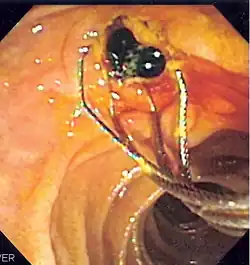

![]() Duodenoscopic image of two black pigment stones extracted from common bile duct after sphincterotomy | |

When needed, the sphincters of the ampulla and bile ducts can be enlarged by a cut (sphincterotomy) with an electrified wire called a sphincterotome for access into either so that gallstones may be removed or other therapy performed.[10]

Other procedures associated with ERCP include the trawling of the common bile duct with a basket or balloon to remove gallstones and the insertion of a plastic stent to assist the drainage of bile.[11] Also, the pancreatic duct can be cannulated and stents be inserted.

In specific cases, other specialized or ancillary endoscopes may be used for ERCP. These include mother-baby and SpyGlass cholangioscopes (to help in diagnosis by directly visualizing the duct as opposed to only obtaining X-ray images[13][14][15]) as well as balloon enteroscopes (e.g. in patients that have previously undergone digestive system surgery with post-Whipple or Roux-en-Y surgical anatomy).[16]